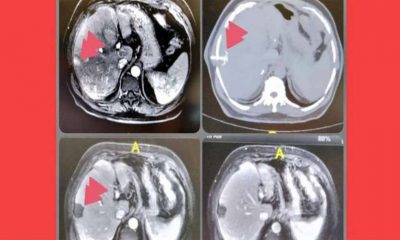

Chamada de ablação, a técnica utiliza radiação micro-ondas para "torrar" as células cancerígenas